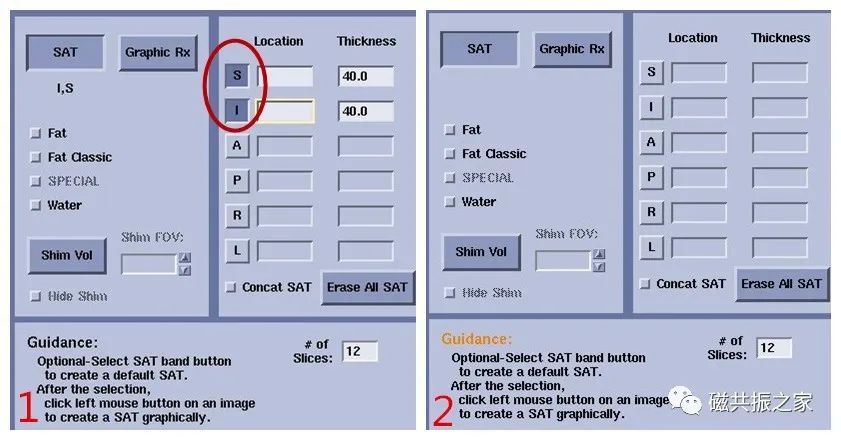

同样,某项成像选项也会使TR延长,导致成像时间的增加,如去除该选项则会减少扫描时间。在T1WI序列尤为明显,如下图:

图1,加了S和I饱和带后,TR延长了,扫描时间为3:40。图2,去除饱和带后,TR缩短了,扫描时间为2:10。